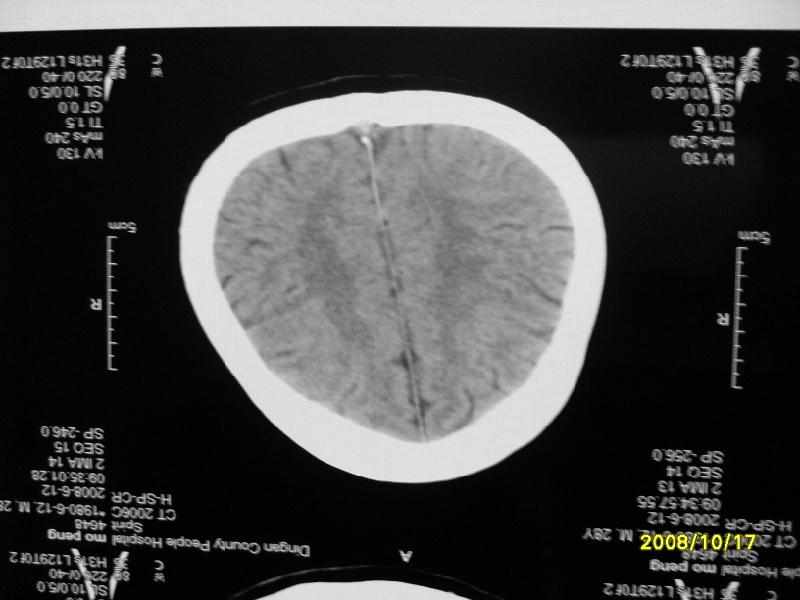

检查名称:     ct颅脑平扫           男     28岁

表现:左顶叶见斑点状致密影。边缘清,大小约0。3*1。0cm,余脑实质密度及灰白质结构示见异常。脑室系统大小,形态,密度未见异常。脑沟。脑裂。脑池未见异常密度影。中线结构无移位。

印象:左顶叶少许钙化灶

左顶叶见斑点状致密影。边缘清,大小约0。3*1。0cm,余脑实质密度及灰白质结构示见异常。脑室系统大小,形态,密度未见异常。脑沟。脑裂。脑池未见异常密度影。中线结构无移位。

印象:左顶叶少许钙化灶。

镰旁钙化

脑沟钙化,考虑陈旧性炎症后

考虑脑膜钙化或脑膜血管钙化

镰旁钙化或顶骨内板骨嵴部分容积效应,建议mri矢状位扫描观察与顶骨的关系。排外后者。

左顶叶见斑点状致密影